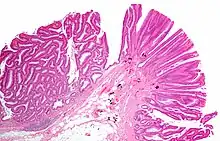

Micrograph of a colorectal villous adenoma. H&E stain

These adenomas may become malignant (cancerous). Villous adenomas have been demonstrated to contain malignant portions in about 15–25% of cases, approaching 40% in those over 4 cm in diameter.[7] Colonic resection may be required for large lesions. These can also lead to secretory diarrhea with large volume liquid stools with few formed elements. They are commonly described as secreting large amounts of mucus, resulting in hypokalaemia in patients. On endoscopy, a "cauliflower' like mass is described due to villi stretching. Being an adenoma, the mass is covered in columnar epithelial cells.